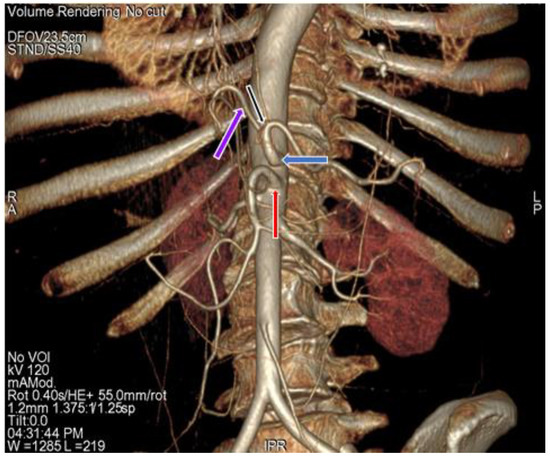

3.1. Variation in Origin and Branching Pattern of Celiac Trunk

3.2. Variation in Origin and Branching Pattern of Hepatic Artery